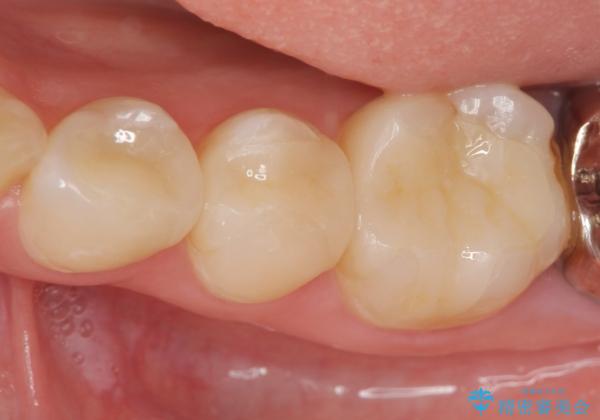

- 23.1万円 セラミックインレー×3費用は治療当時の料金となります

天然の歯のような色調を再現したセラミック修復処置を行ったことで口腔内の目立つ銀歯がなくなり満足いただくことができました。